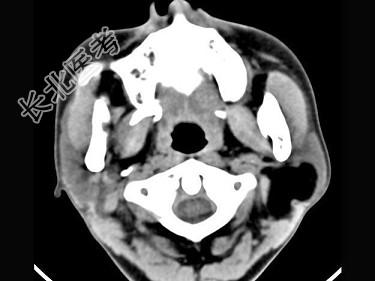

- 多项选择题男,38岁, 左侧腮腺渐进性肿大1年,无压痛, CT扫描如图所示,正确的描述或诊断是 ( )

A、左侧腮腺区见低密度肿块,CT值约为-200Hu

B、肿块边缘清楚,未见邻近结构受侵

C、囊肿

D、脂肪瘤